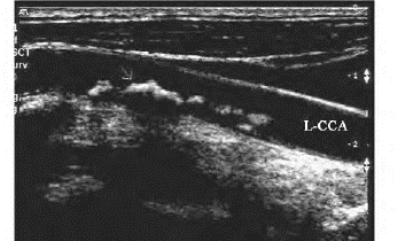

1.26.3三、正常血管

1.26.4四、动脉闭塞性疾病